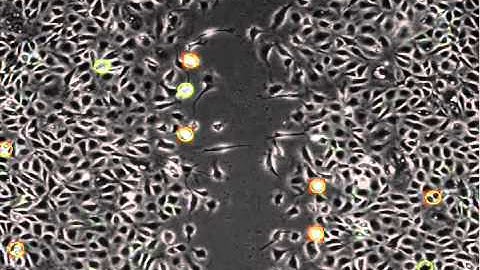

Automated mitosis detection in phase contrast microscopy